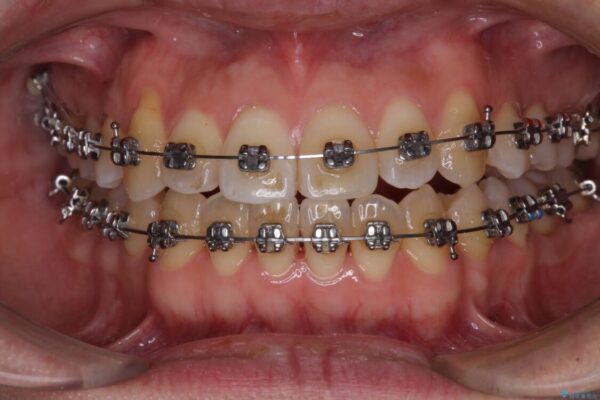

治療途中

• 左右の八重歯が気になる ワイヤー装置での咬み合わせ改善 治療途中画像

営業職であり、商談などで飲食をする機会が多いとのことで、インビザラインではなく、ワイヤー装置にて矯正治療を行うこととしました。